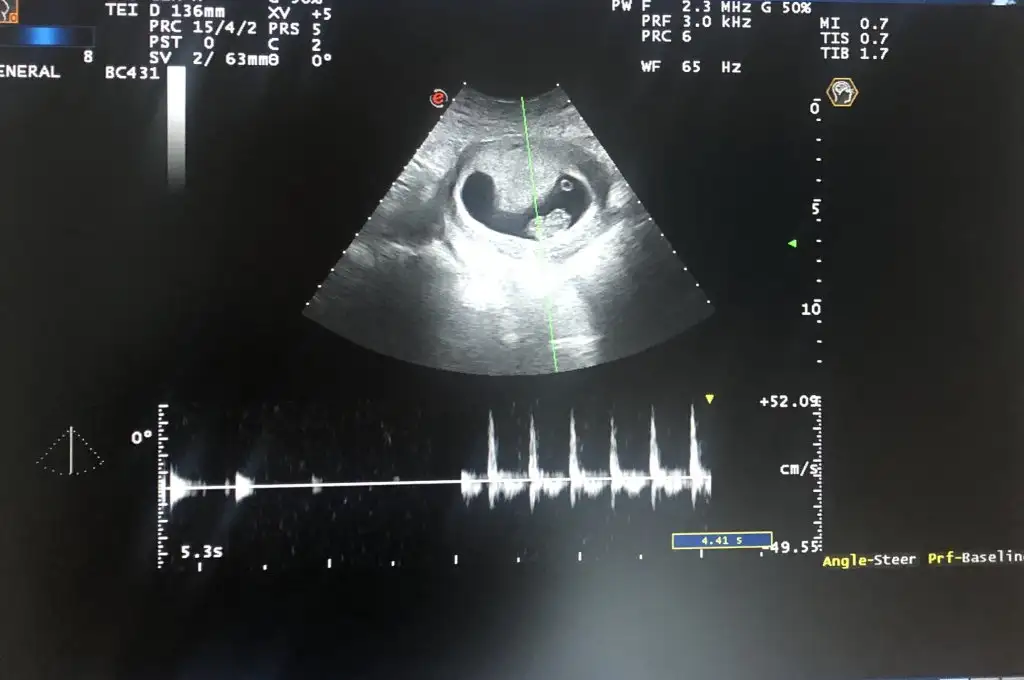

Kuzum tam ortada duruyor ya bilemedim yanlış bir şey söylemek istemiyorum 6 haftalım yok mu